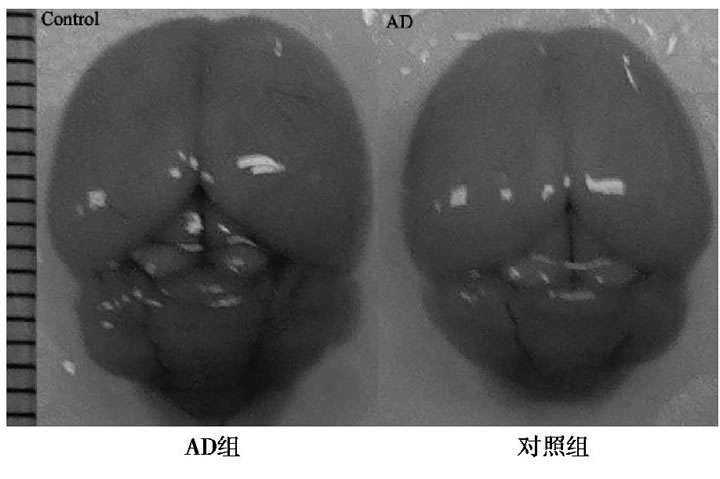

2.1 AD和對照組全腦圖

與對照組比較, AD小鼠完整腦組織表面泛白、無血色, 血管明顯減少, 表明D-半乳糖聯(lián)合三氯化鋁已經對小鼠的腦組織形成退行性損傷。見圖1。

圖1 AD組和對照組小鼠全腦圖